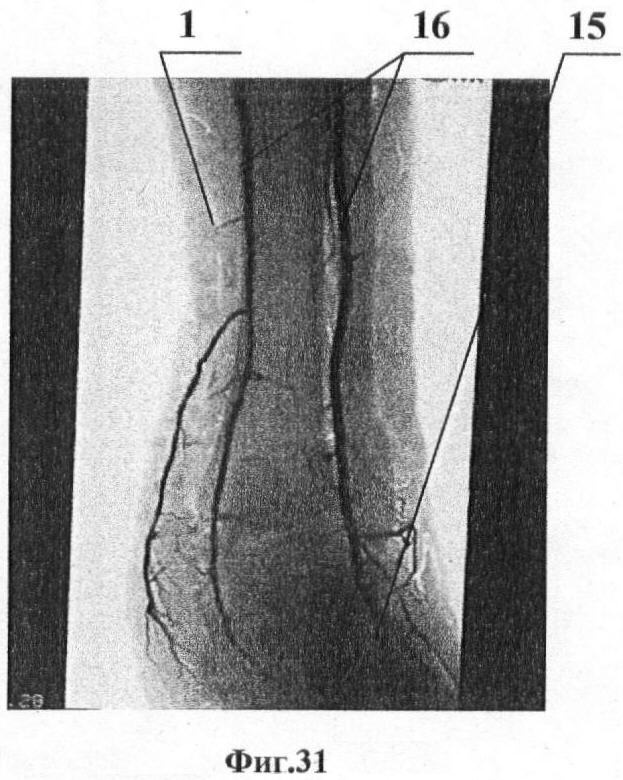

Поскольку иллюстративные материалы в отличие от описания и формулы изобретения не имеют правового значения, носят факультативный характер и представляются лишь для более ясного и четкого понимания обязательных элементов заявки (Коментарий к Гражданскому Кодексу Российской Федерации, часть четвертая, ст.1375, п.8, изд. Проспект, 2007), ход и схема выполнения оперативного вмешательства по заявленному способу представлены ниже в виде рисунков и фотографий. На рисунках показано: на фиг.1 показан доступ для эндоскопического забора лоскута передней зубчатой мышцы; на фиг.2 – рамка кольцевой формы; на фиг.3 – рамка криволинейной формы; на фиг.4. – внешний вид тракционного механизма; на фиг.5 – подвеска груза, кожа приподнята; на фиг.6 – обнажение переднего края широчайшей мышцы спины и наружной поверхности передней зубчатой мышцы; на фиг.7 – выделение первого сосуда; на фиг.8 – выделенные и идентифицированные сосуды взяты на держалки; на фиг.9 – передний край широчайшей мышцы спины приподнят, сосуды идентифицированы, проксимальная диссекция сосудистой ножки, дополнительный проксимальный портал; на фиг.10 – начало диссекции в поверхностной фасциальной расщелине; на фиг.11 – окончание диссекции в поверхностной фасциальной расщелине; на фиг.12 – выкраивание мышечной части лоскута, дополнительный дистальный портал; на фиг.13 – начало диссекции в глубокой фасциальной расщелине; на фиг.14 – окончание диссекции в глубокой фасциальной расщелине; на фиг.15 – лоскут извлечен из нативного места, гемостаз донорского ложа; на фиг.16 – лоскут готов к транспонированию, сосудистую ножку сохраняют до окончательной подготовки реципиентных сосудов; на фиг.17 – основной и дополнительные порталы ушиты, аспирационное дренирование; на фиг.18 – транспонирование и подгонка лоскута; на фиг.19 – реконструируирование мягкотканого дефекта, замещение дефекта лоскутом. На фотографиях показано: фиг.20 – раненый Г., рубцовый дефект левой пяточной области; фиг.21 – раненый Г., рентгенограммы стопы, остеомиелит пяточной кости, снижение угла Белера; фиг.22 – раненый Г., предоперационная разметка реципиентной области; фиг.23 – раненый Г., предоперационная разметка донорской области; фиг.24 – раненый Г., положение больного на операционном столе; фиг.25 – раненый Г., выделение первого сосуда через основной портал; фиг.26 – раненый Г., эндоскопическая диссекция сосудистой ножки; фиг.27 – раненый Г., выкраивание мышечной части лоскута; фиг.28 – раненый Г., лоскут передней зубчатой мышцы извлечен из нативного места; фиг.29 – раненый Г., микрососудистый шов по типу «конец-в-конец» артерии (красная стрелка) и вены (синяя стрелка); фиг.30 – раненый Г., лоскут укрыт расщепленным кожным трансплантатом; фиг.31 – раненый Г., артериограмма области реконструкции; фиг.32 – раненый Г., внешний вид области реконструкции через 1 месяц после операции; фиг.33 – раненый Г., внешний вид и функция донорской области через 6 месяцев после операции, рука поднята; фиг.34 – раненый Г., внешний вид и функция донорской области через 6 месяцев после операции, рука опущена.

После этого перевязывают торакодорзальную артерию и коммитантные вены, после отхождения зубчатой ветви торакодорзальный нерв оставляют интактным, для этого его предварительно отделяют от сосудистой ножки (фиг.9) и отводят в сторону, входят в поверхностную фасциальную расщелину между передней зубчатой мышцей и подкожно-жировой клетчаткой. При поднятых краях кожи 11 выполняют диссекцию по поверхности передней зубчатой мышцы (фиг.10), а затем определяют нижние зубцы мышцы, васкуляризируемые ветвью торакодорзальной артерии к передней зубчатой мышце. Выполняют тупую диссекцию над каудальным краем верхнего зубца, кровоснабжаемого сосудистой ножкой. Входят в глубокую фасциальную расщелину (фиг.11) между передней зубчатой мышцей и реберной фасцией и выкраивают мышечную часть монолоскута 12 (фиг.12) по периферии, при этом внутримышечные сосудистые ветви клиппируют, для чего создают дополнительный портал (фиг.13). Осуществляют окончательную мобилизацию лоскута 12 (фиг.14) и вытягивают его через основной портал, при этом под эндоскопическим контролем пересекают сосудистую ножку на проксимальном уровне, перевязывают или клиппируют ее ветви (фиг.16), одновременно контролируют гемостаз (фиг.15) и налаживают аспирационное дренирование донорского ложа аппаратом 13 (фиг.17). Послойно ушивают основной и дополнительные порталы, после чего указанным лоскутом замещают мягкотканый дефект, соединяют его сосуды с сосудами реконструируемой части тела пациента (фиг.17). Дальнейший процесс лечения мягкотканого дефекта, например, в области пятки заключается в том, что лоскут 12 (фиг.18) транспонируют в область реконструируемого мягкотканого дефекта 14 (фиг.19), замещают им мягкотканый дефект и соединяют сосуды 15 лоскута с сосудами 16 реконструируемой области и наложением соответствующих швов 17 и укрыванием кожным трансплантантом 18.

Пациент Г., получил осколочное ранение левой пяточной области во время вооруженного конфликта на Северном Кавказе в 1999 году. Раневой процесс осложнился хроническим огнестрельным остеомиелитом пяточной кости, сопряженным с мягкотканым дефектом нагружаемой поверхности пяточной области. В лечебных учреждениях выполнялась дерматотензия и пластика местными тканями. Несмотря на купированный остеомиелитический процесс и эпителизацию раны возникший рубцовый дефект размерами 7×5 см нагружаемой зоны служил причиной значительных функциональных нарушений конечности (фиг.20, фиг.21). После предоперационного планирования (фиг.22-23 в положении больного на боку (фиг.24) были иссечены рубцы и подготовлены к анастомозированию сосуды в реципиентном ложе. Далее выполнен эндоскопический забор свободного лоскута передней зубчатой мышцы (фиг.25 – фиг.38). Лоскут транспонирован в реципиентное ложе, выполнено микрососудистое анастомозирование (фиг.29), а сам лоскут покрыт расщепленным аутодермотрансплантатом 18 (фиг.30). Реконструкция лоскута была состоятельной (фиг.31, фиг.32), послеоперационный период протекал без осложнений, а морбидность донорского места 19 (фиг.33, фиг.34) оценена как низкая, а перфузия лоскута состоятельна, дефект реконструирован с удовлетворительным результатом.